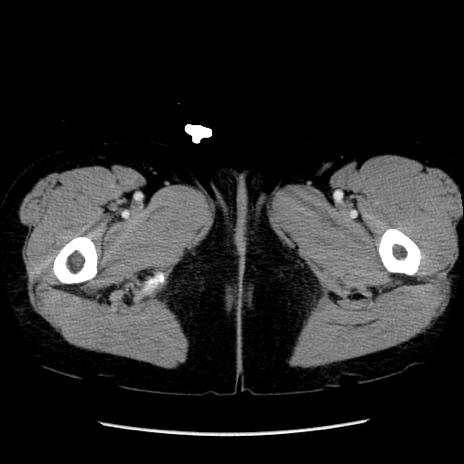

冠状断像